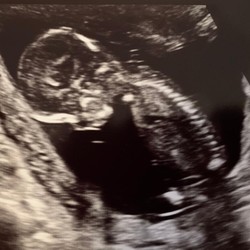

Ik zocht hierop omdat ik nu 4+5 zwanger ben en vorig jaar twee keer een lisexcisie heb gehad, eerste keer was er te weinig weg gehaald en bleek dat ik baarmoederhalskanker had (gelukkig beginnend en niet verder gevorderd). Dit was na een curettage (MA bij 10 weken :( ) daaruit bleek dat er onrustige cellen waren gevonden. Daarna tweede keer een lis behandeling gehad waarbij er ruimer is weggehaald, snijranden leken voor zover beoordeelbaar schoon, na half jaar uitstrijkje en toen eindelijk goed nieuws! Ik ben zelf ook benieuwd of dit van invloed zal zijn tijdens mijn zwangerschap. De gynaecoloog heeft aangegeven dat mijn baarmoederhals meerdere keren moet worden opgemeten via de verloskundige. Ben benieuwd maar eerst de echo’s afwachten :)

Achteraf was ik tijdens de tweede al zwanger, vier weken na de laatste behandeling bleek ik al zes weken zwanger te zijn!

Ik ben nu onder controle van een gynaecoloog, omdat je baarnmoederhals verkort kan zijn. Dit is bij mij tot nu toe gelukkig niet het geval. Maar ik moet elke zes weken terug komen en de gynaecoloog blijft het in de gaten houden.

Hey, ik heb in februari een lisexcie gehad en ook ik raakte onverwachts zwanger, nu 18 weken :-)